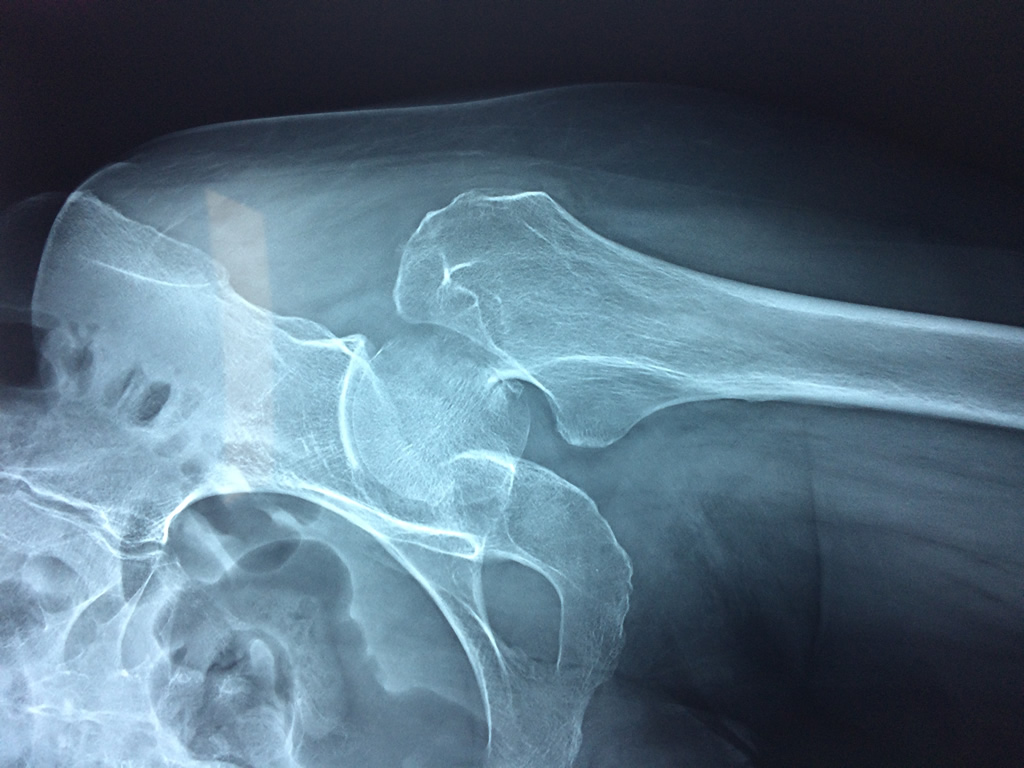

Cirugías de Húmero - Cadera

La cirugía de fractura de cadera se realiza para reparar una ruptura en la parte superior del hueso del muslo. Este hueso se denomina fémur.